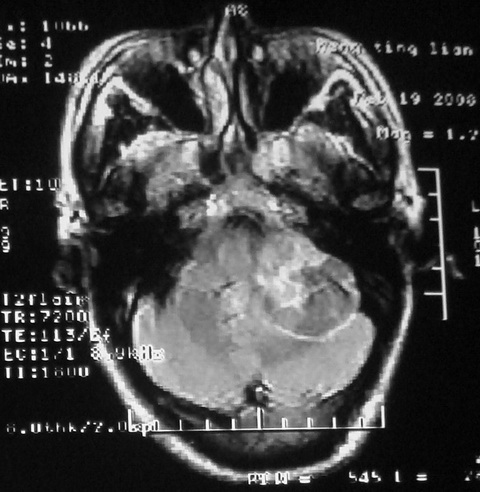

m,72,头疼,头晕两年,伴视力模糊三月,饮食呛咳两天。pe:颈部抵抗,左眼突出,左眼瞳孔约3mm,对光反射消失,双眼失明,伸舌困难,双肺呼吸音粗,心率110次/分,左上肢肌力i级,左下肢屈曲,肌张力高。现有08年2月19mri平扫及10年2月8日mri增强请会诊。ct病灶呈低密度伴散在点、片状等密度区,无明确钙化(无ct片资料可供上传)。[

脑外肿瘤,表皮样囊肿可能性大。

考虑表皮样囊肿。

脑外肿瘤,病灶呈匍匐蔓延,表皮样囊肿可能性大。

脑外肿瘤,病灶呈匍匐蔓延,表皮样囊肿可能性大。支持!